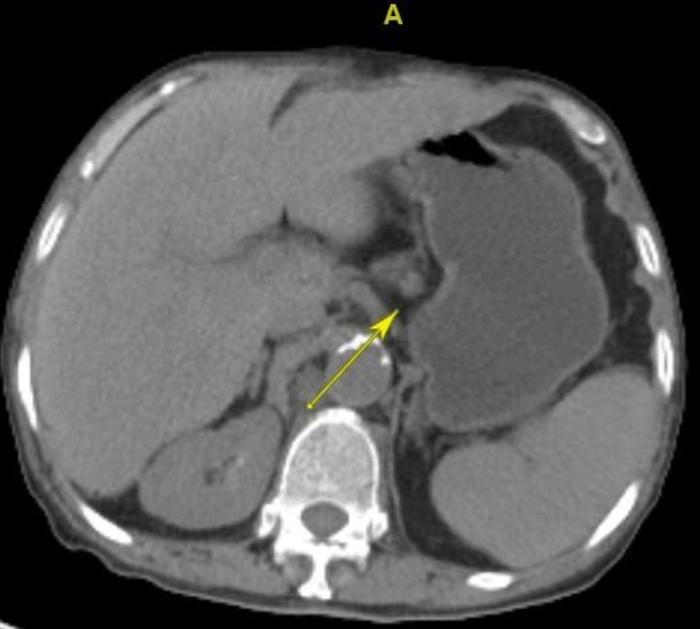

这个病人,没有肺癌,会不会有食管癌呢?

上图箭头指示的是食管粘膜面粗糙,小颗粒样隆起。